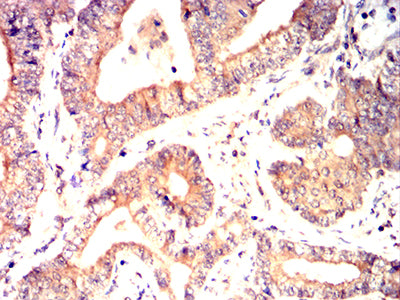

- Immunohistochemical analysis of paraffin-embedded human lung cancer tissues using C9orf72 mouse mAb with DAB staining.